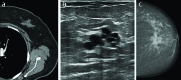

Objective: Although mammography is the primary imaging method of the breast, incidental benign and malignant breast lesions are increasingly being detected on computed tomographies (CTs) performed to detect different pathologies. Therefore, the detection and accurate identification of these lesions is important. In this study, we aimed to evaluate the frequency, morphological features, and results of incidental breast lesions on CTs performed for the detection of extramammarian pathologies.

Results: The study population consisted of 33 women whose mean age was 55±1.38 (37-78) years. Of the 33 women, 12 (36%) had malignant and 21 (64%) had benign or normal findings. The most common malignant lesion was invasive ductal carcinoma, and the most common benign lesion was fibroadenoma. Ill-defined contour and lymphadenopathy in malignant lesions and well-defined contour in benign lesions were the most important CT findings.

Conclusion: Breast must be carefully evaluated if it is included in the scans. An accurate report of breast lesions gives an opportunity for early diagnosis and treatment.